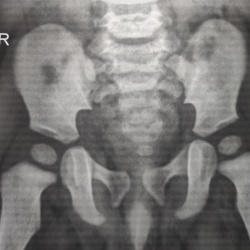

Ребенку 9 месяцев, обследование на дисплазию. Смутил краевой дефект в области большого вертела левой бедренной кости, выклядит как просветление неправильной формы с ободком. Накручиваю себя? Что...

Здравствуйте! Женщина, 60 лет, жалобы на боли в тазобедренных суставах. На рентгенограмме в проекциях подвздошных костей выявлены дополнительные участки склероза. Что это может быть?

Беспокоят боли в правом т/б суставе.